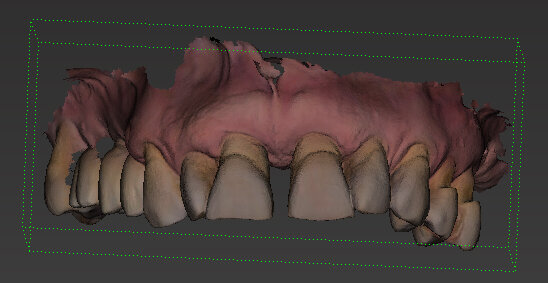

All’esame clinico presenta i quattro incisivi superiori malposizionati, con diastema per evidenti problemi parodontali. Perdita importante di supporto parodontale, presenza di tasche superiori a 6 mm, mobilità di tipo 2/3 su tutti i quattro elementi (Figg. 1-4).

Il piano di trattamento prevede l’estrazione degli elementi dentali, l’inserimento di due impianti e la realizzazione di una protesi fissa di quattro elementi. Il problema da gestire è quello della fase provvisoria. Non è ipotizzabile una protesi mobile e quindi programmiamo di inserire subito dopo l’intervento un provvisorio immediato. Questo ci consente di condizionare da subito i tessuti periimplantari e anche le zone dei ponti. Si rileva un’impronta digitale (Figg. 5, 6), e la programmazione degli impianti viene effettuata con un software di chirurgia guidata (Fig. 7) e la posizione degli impianti nello spazio biologico e nello spazio protesico viene fatta sulla base di una ceratura diagnostica (Figg. 8, 9). Inseriamo gli impianti virtuali nell’osso disponibile (Figg. 10-13) e in relazione all’aspetto protesico correggiamo l’asse di inclinazione degli impianti con componenti secondarie angolate a 17° (Figg. 14, 15). Questo ci consentirà di realizzare una protesi avvitata con i fori situati nella zona palatale.

Fig. 5 - Impronta iniziale digitale.